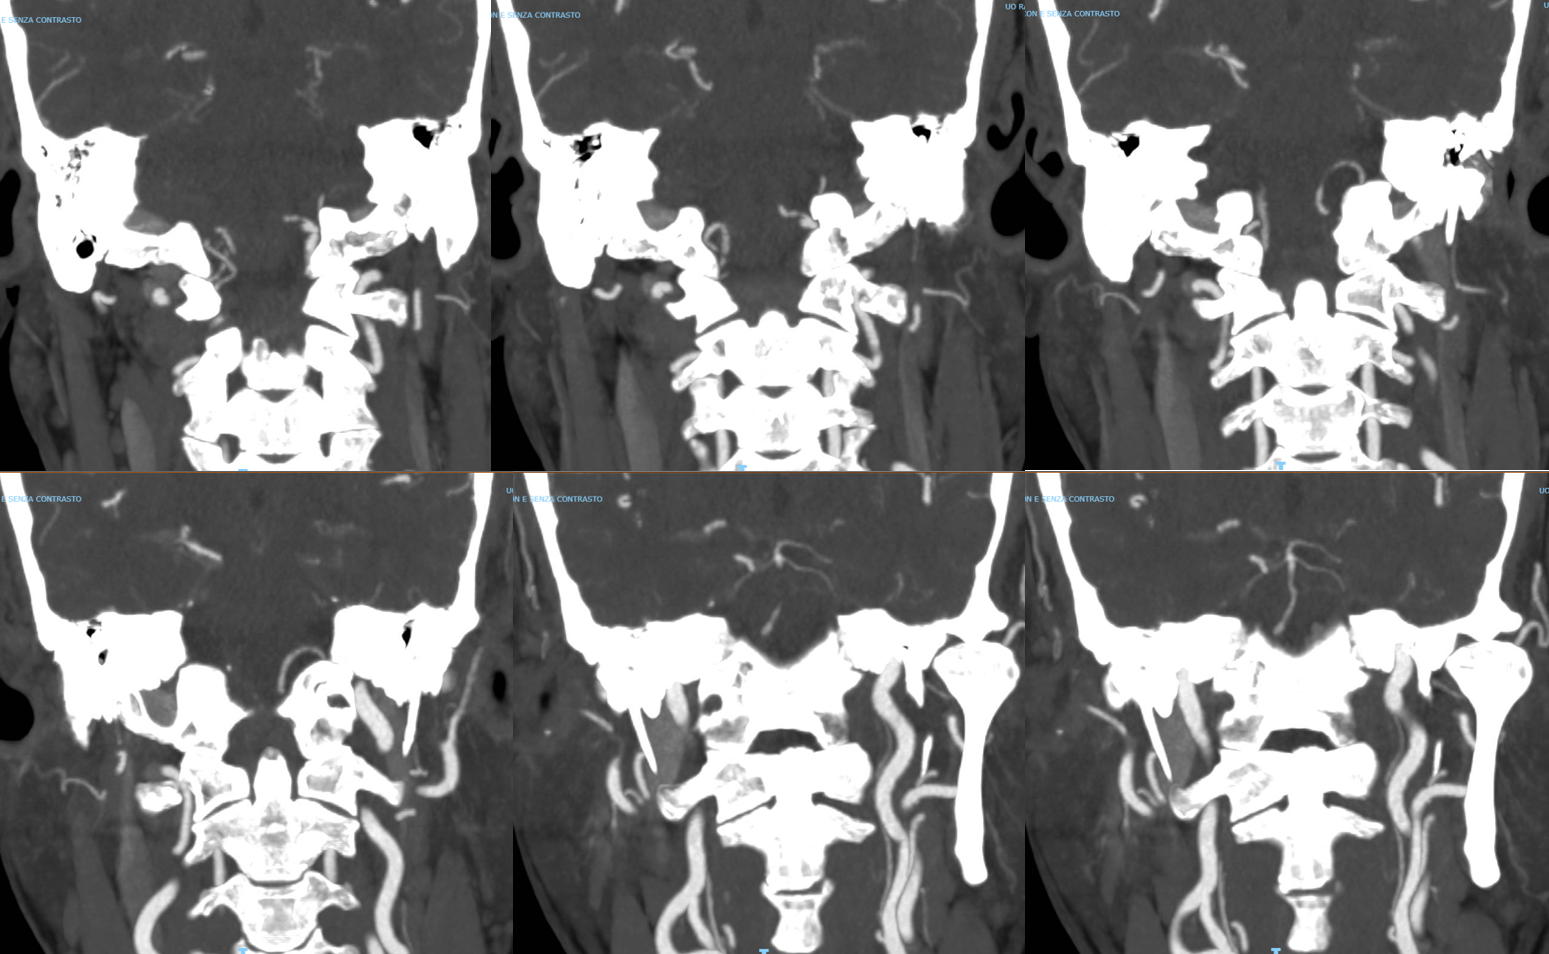

This video below is the fusion of Vaso-CT (protocol 22 cm FOV, 20 seconds acquisition, 20 ml pure contrast (250 mg/ml) manual injection, reconstructed with 50% FOV and 5123 matrix) of the left (blue) and right (red) vert.

In faint blue we see the walls of the occluded part of the left vert (much larger than the right vert). Viewing the walls blue means that they are vascularized with the injection of the left vert (vasa vasorum). A mix of calcification and vasa vasorum is possible — see below. The basilar artery is almost white because it receives contrast with the injection of both vertebral arteries. Bone is also shades of grey.

Snapshots. The course of the closed vert shows that recanalization is better from the left.

The simplest way to tell calcium from vasa vasorum is to get a noncontrast “mask” image. In this case, the below image shows right vert injection which serves as the mask for the left vert, on the left, and left vert injection image on the right. There is some calcification in the wall of the occluded distal left vert, but the wall is much more visible with the left vert injection, due to vasa vasorum.